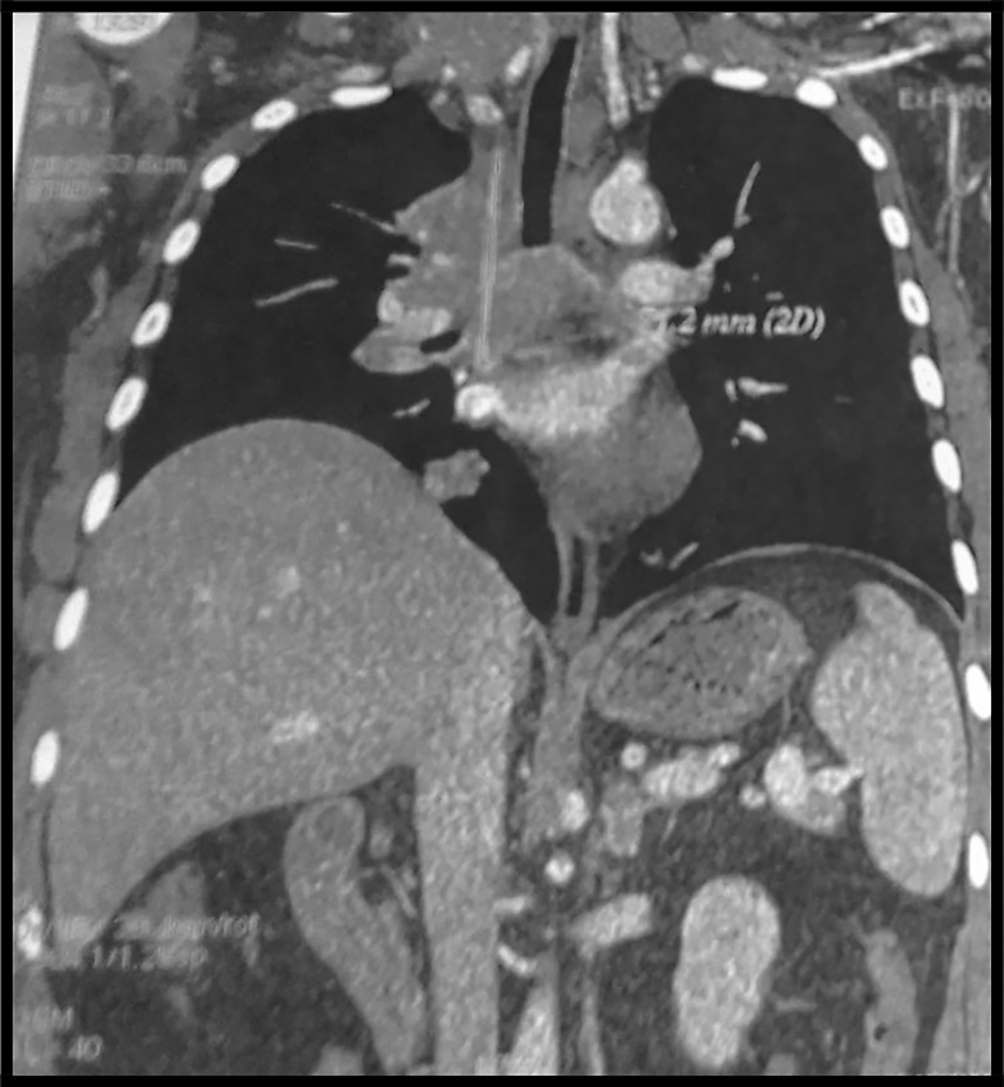

The body computed tomography (CT) scans revealed a bulky mediastino-hilar tumor in the right chest, measuring (90 x 85 x 71 mm), invading the right main bronchus, extending to the vena cava and infiltrating the pericardium with a subpleural right node (Figures 2 and 3). Bronchoscopy showed a polypoid mass located in the carina, involving the right main bronchus. Cytology revealed malignant cells. Histopathology of the bronchial biopsy did not show any malignant lesions. In addition, we performed a biopsy of the supra-clavicular adenopathy. Histopathology revealed an intense staining for CD15 and CD30 with large multinuclear reed Sternberg cells. Therefore, the diagnosis of an Hodgkin lymphoma was confirmed.